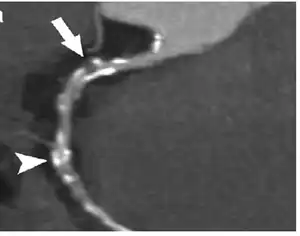

Coronary Computed Tomography Angiography (CCTA)

Computed tomography angiography (CTA), an imaging methodology using a ring-shaped machine with an X-ray source spinning around the circular path so as to bathe the inner circle with a uniform and known X-ray density. Cardiology uses are growing with the incredible developments in CT technology. Currently, multidetector CT, specially the 64 detector-CT are allowing to make cardiac studies in just a few seconds (less than 10 seconds, depending on the equipment and protocol used). These images are reconstructed using algorithms and software.

Gated Cardiac CT (CCT)

Cardiac CT (CCT) is a modified form of the traditional chest CT due to the difficulty of imaging the complex, moving heart.[16] This is achieved through the use of thin slices and high-resolution scanning, as well as the addition of electrocardiogram (ECG) gating or triggering to capture a motion-free image. Standard CT scans are acquired in either Axial or Helical modes, while CCT adds the ECG gating dimension to these modes to capture images of the heart.[16] These modifications are necessary to obtain the required data from the planar slice images, which are reconstructed from back-projected transmitted data obtained by radial excursion of the X-ray tube and detector.[16]

Coronary CT calcium scan

A coronary CT calcium scan is a computed tomography (CT) scan of the heart for the assessment of severity of coronary artery disease. Specifically, it looks for calcium deposits in the coronary arteries that can narrow arteries and increase the risk of heart attack.[17] This severity can be presented as Agatston score or Coronary Artery Calcium (CAC) score. The CAC score is an independent marker of risk for cardiac events, cardiac mortality, and all-cause mortality.[18] In addition, it provides additional prognostic information to other cardiovascular risk markers.[18] A typical coronary CT calcium scan is done without the use of radiocontrast dye, but it can possibly be done from contrast-enhanced images as well, such as in coronary CT angiography.[19]